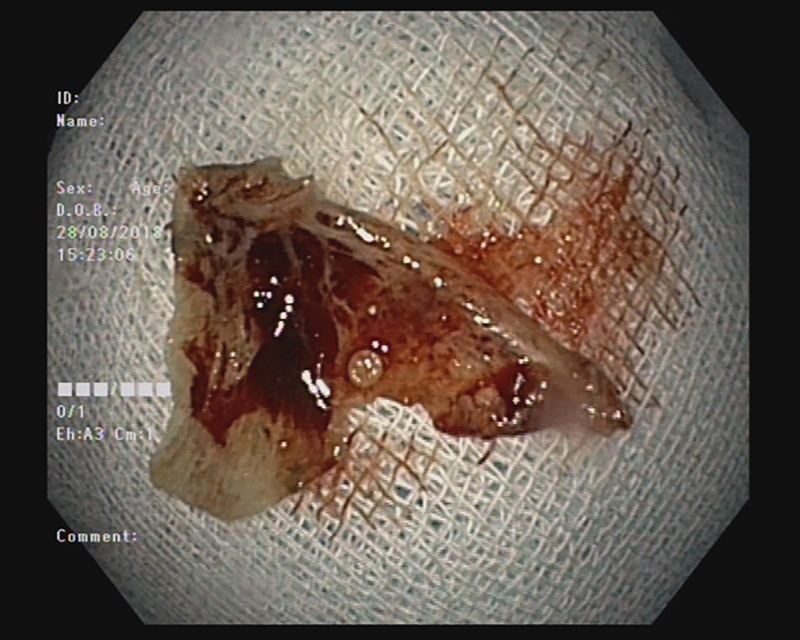

Đây có thể được coi là ca tai nạn sinh hoạt hy hữu mà BV trên tiếp nhận. Bệnh nhân vào BVXA-VL cấp cứu trong tình trạng khó chịu và đau cổ dữ dội. Sau khi thăm khám kỹ lưỡng, kiểm tra trên lâm sàng và nội soi, các bác sĩ phát hiện có hình ảnh của một mảnh xương cá nằm tại vị trí miệng thực quản.

Ngay sau đó các bác sĩ trung tâm nội soi tiến hành nội soi gắp xương cá. Hiện tại, tình trạng sức khỏe bệnh nhân đã ổn định và đã xuất viện trong ngày.

Các bác sĩ cho biết, mặc dù, xương cá là một dị vật thường gặp và đơn giản, nhưng nếu không được xử trí lấy dị vật ra kịp thời thì có thể sẽ xảy ra các tình huống nguy hiểm như dị vật đâm rách, thủng thực quản dẫn đến áp xe thực quản. Ổ áp xe có thể vỡ vào trung thất gây nguy hiểm đến tính mạng nhiều trường hợp có thể dẫn đến tử vong. Dị vật có thể di chuyển theo đường tiêu hóa xuống ruột gây tổn thương như rách thủng niêm mạc ruột, tắc ruột ảnh hưởng lớn tới sức khỏe. Khi đó việc can thiệp lấy ra bằng phương pháp nội soi vô cùng khó khăn thậm chí bệnh nhân phải trải qua một cuộc phẫu thuật phức tạp hơn.